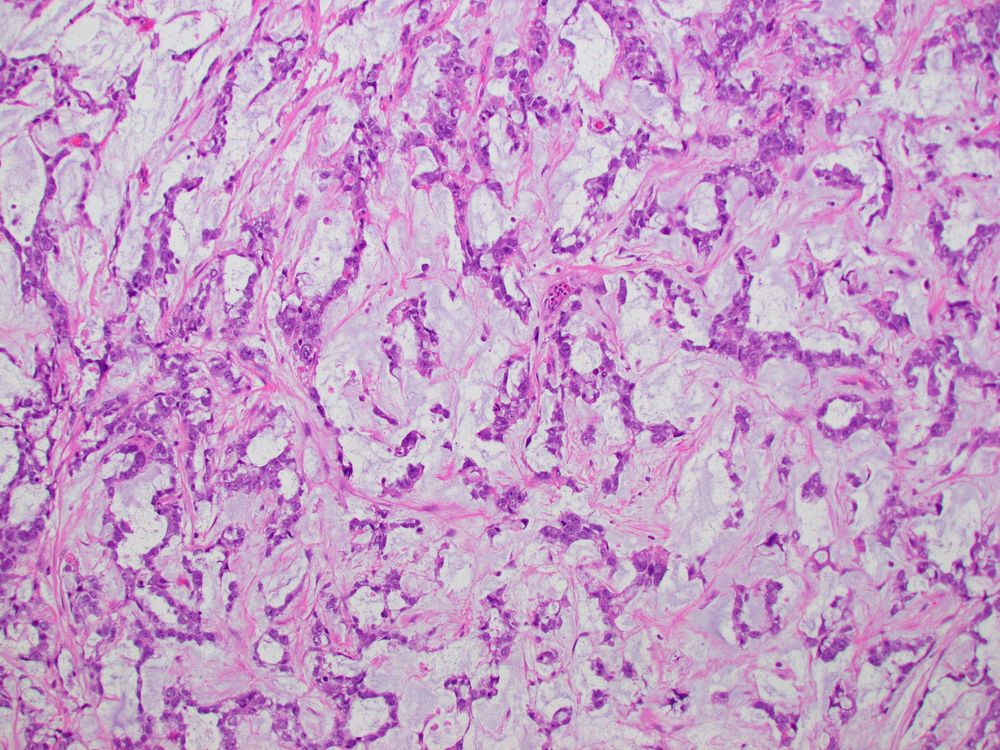

Lymphangioleiomyomatosis:

1. Yet another misnomer in #pulmpath

2. PEComatous proliferations in walls of lung cysts

3. ALWAYS consider in women with bilateral lung cysts, recurrent pneumothoraces, tuberous sclerosis or renal angiomyolipoma

4. VERY IMPORTANT for boards

#pathsky